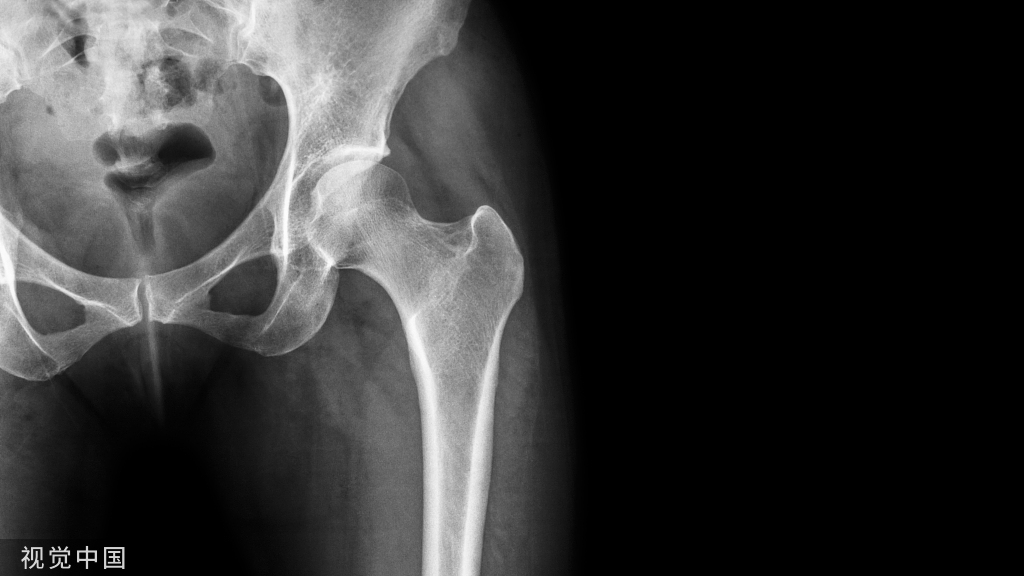

骨质疏松其实是由于骨量降低、骨组织微结构被破坏、骨脆性增加,让骨头里面的结构缝隙越来越大,骨骼变得越来越脆弱,并引起驼背、全身疼痛、骨折等情况。

“骨质疏松症”的诊断分为临床诊断和仪器诊断。如果病人已经发生“脆性骨折”,即在轻微外力的作用下就发生骨折,如咳嗽两声就导致肋骨的骨折,下楼梯仅仅踩空一下没有摔倒就导致小腿骨折,这种情况不做骨密度检查就可以直接诊断为骨质疏松症。但是对于没有发生骨折的病人,则需要借助骨密度检查来诊断骨质疏松症。检查方法是用双能X线骨密度仪检查腰椎和股骨颈的骨密度。